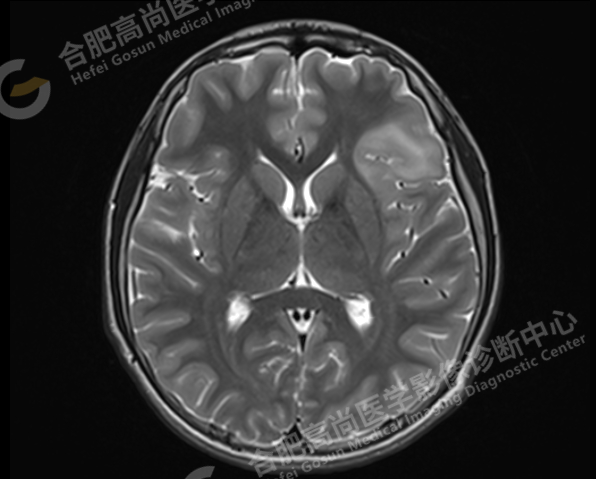

左侧额中、下回显示局灶性脑皮质较肿胀,呈长 T1 长 T2 信号影,FLAIR 显示皮层下高信号,DWI 未见异常高信号影,冠状位观察:病变主要累及皮层及皮层下白质,并见皮层增厚,皮白质分界模糊,未见明显放射带。余双侧大脑半球对称,灰白质对比正常,幕上脑室系统未见大,中线结构居中,脑沟、脑池蛛网膜未见增宽。矢状位示腺垂体变扁,垂体窝空虚,神经垂体高信号位置如常。扫及腺样体增厚,信号均匀,A/N 值约 0.6。

1. 左侧额中、下回异常信号,考虑为 FCD 高信号型(局灶性脑皮层发育不良)